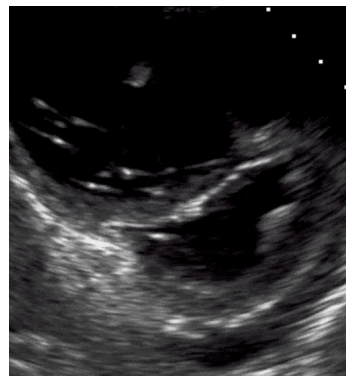

Paciente de 47 anos de idade, previamente hígido, internado na enfermaria de clínica médica devido à erisipela em membro inferior direito, inicia, no quinto dia de internação, dispneia e tosse. A equipe realiza USG à beira leito, que evidencia:

• Padrão A em todo hemitórax direito e esquerdo

• Veia cava turgida

• Ausência de derrame pericárdico

• Sinal de McConnel na janela apical 4 câmaras

• E seguinte imagem na janela paraesternal eixo curto

Legenda: D Sign

Com base nessa situação hipotética, assinale a alternativa com o diagnóstico mais provável.